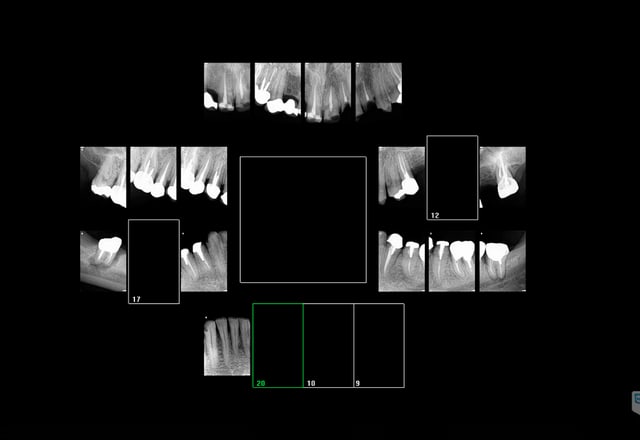

donc tu garantis les reprises de carie sous coiffe?

ou il faut faire des radios pour montrer la bonne adaptation?